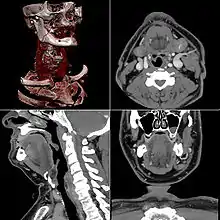

A partir de todas esas imágenes transversales (axiales), un computador reconstruye una imagen bidimensional que permite ver secciones de la pierna (o el objeto de estudio) desde cualquier ángulo. Los equipos modernos permiten incluso hacer reconstrucciones tridimensionales. Estas reconstrucciones son muy útiles en determinadas circunstancias, pero no se emplean en todos los estudios, como podría parecer. Esto es así debido a que el manejo de imágenes tridimensionales no deja de tener sus inconvenientes.

Un ejemplo de imagen tridimensional es la imagen 'real'. Como casi todos los cuerpos son opacos, la interposición de casi cualquier cuerpo entre el observador y el objeto que se desea examinar hace que la visión de este se vea obstaculizada. La representación de las imágenes tridimensionales sería inútil si no fuera posible lograr que cualquier tipo de densidad que se elija no se vea representada, con lo que determinados tejidos se comportan como transparentes. Aun así, para ver completamente un órgano determinado es necesario mirarlo desde diversos ángulos o hacer girar la imagen. Pero incluso entonces veríamos su superficie, no su interior. Para ver su interior debemos hacerlo a través de una imagen de corte asociada al volumen y aun así parte del interior no siempre sería visible. Por esa razón, en general, es más útil estudiar una a una todas las imágenes consecutivas de una secuencia de cortes que recurrir a reconstrucciones en bloque de volúmenes, aunque a primera vista sean más espectaculares.